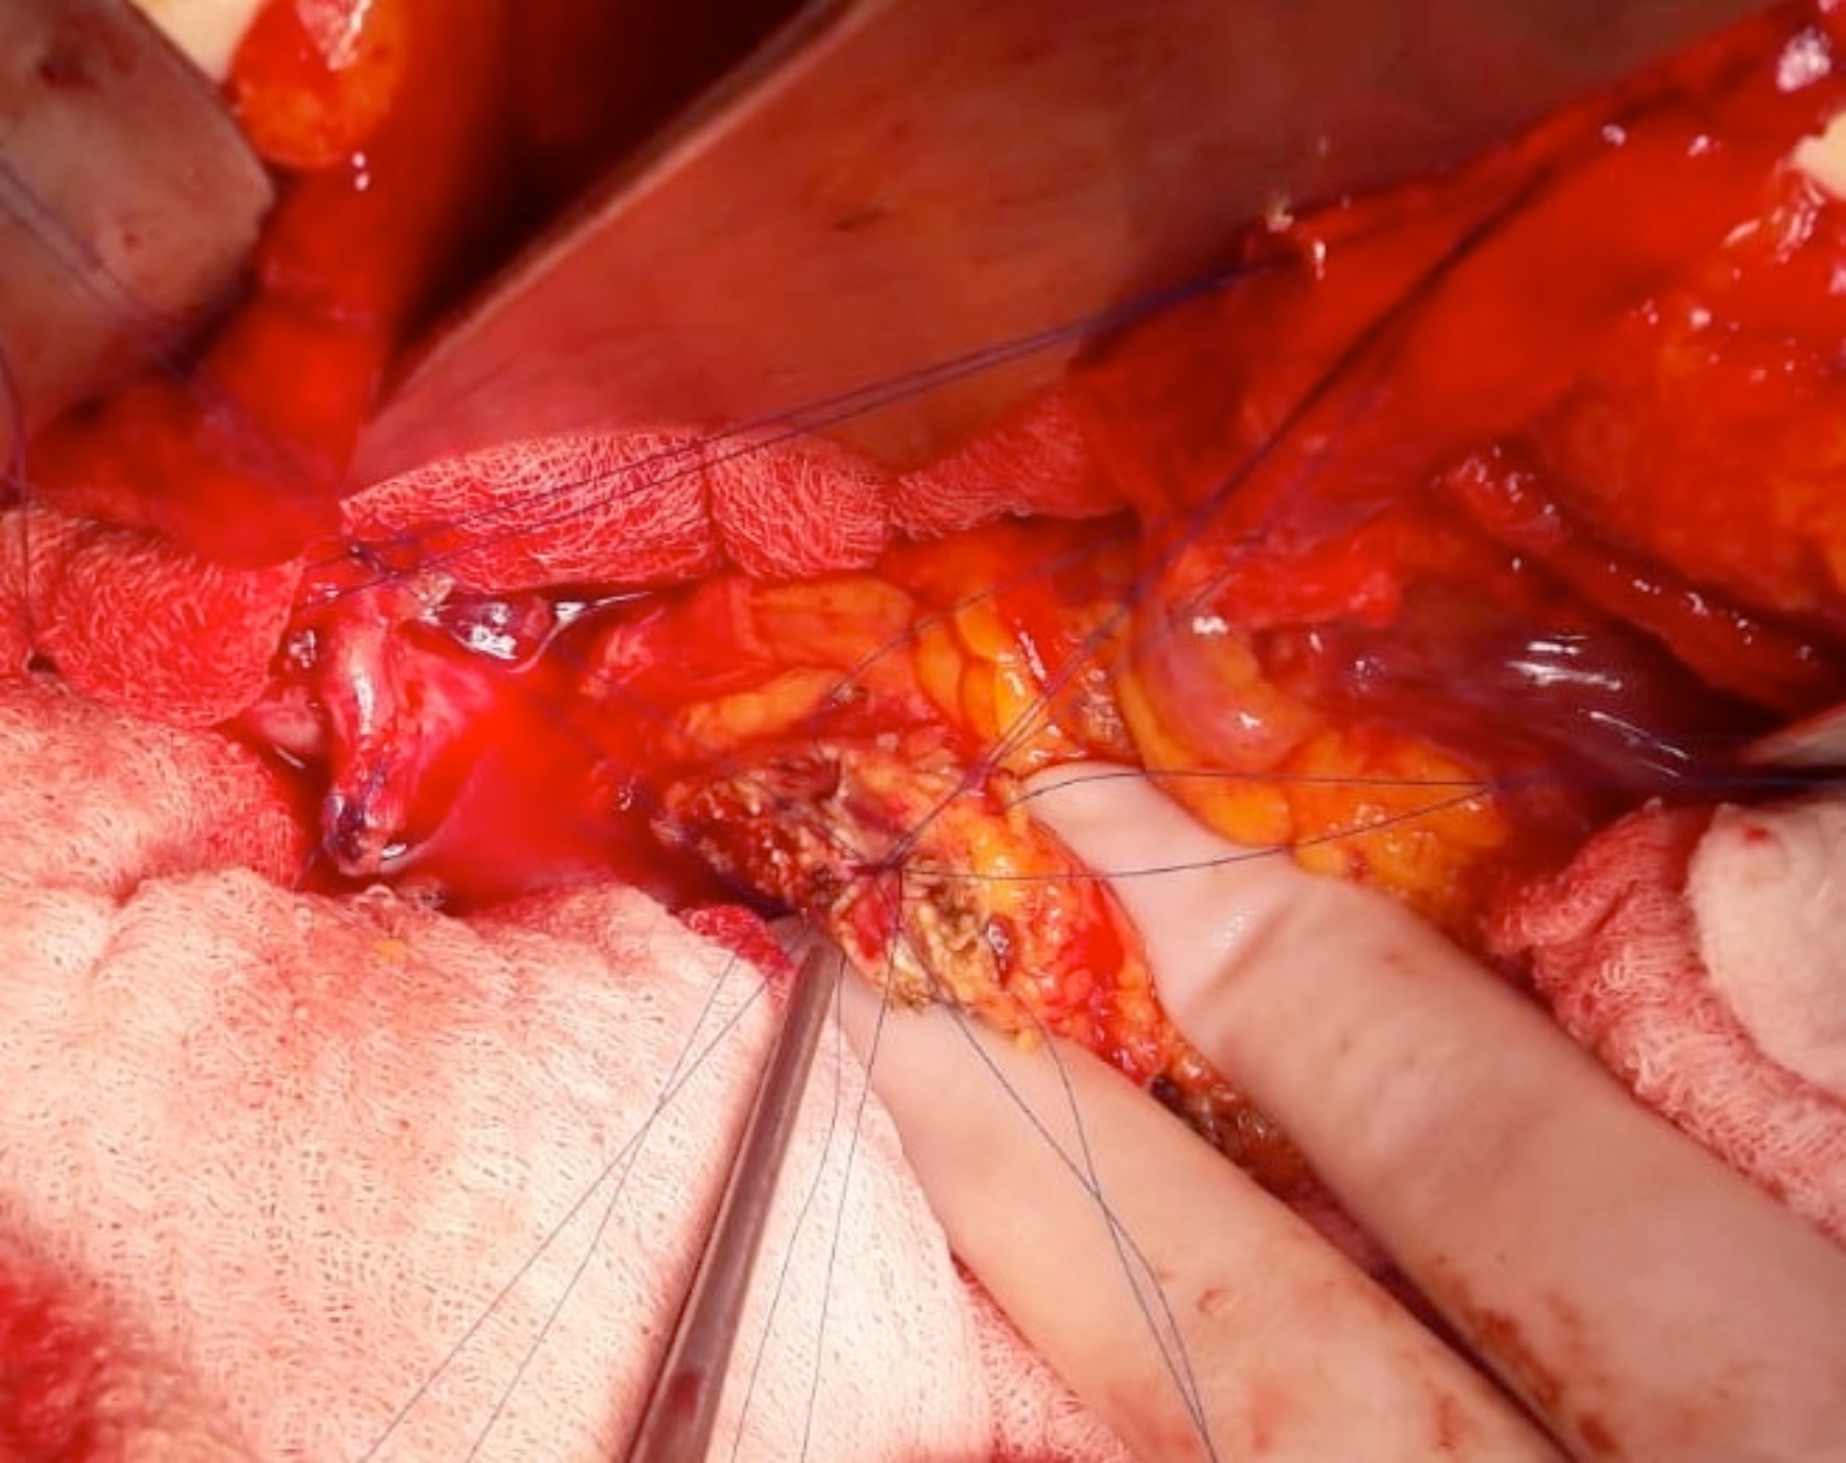

Only two simple interrupted sutures (3/0 absorbable monoflament) were used for the posterior outer layer. Jejunal part was lifted gently from the anterior position and a simple suture was placed between posterior superior and posterior inferior border of the paranchyma of the pancreatic stump and its counterpart of the jejenunal seromuscular layer (Figures 2-3).

Figure 1: Duct-to-mucosa anostomosis inner layer 3-9-5-7-11-12-1 o’clock sutures.

Figure 2: Outer serosal layer posterior superior sutures.

Figure 3: Outer serosal layer posterior inferior sutures.